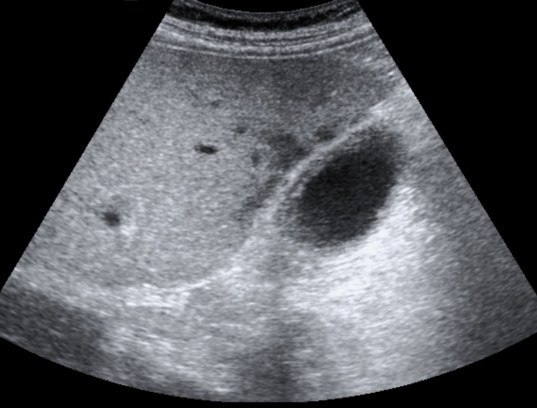

Se realiza ecografía abdominal:

En sucesivos cortes observamos lo siguiente:

Se observa una mala evolución radiológica. Dada la clínica del paciente y los hallazgos ecográficos podemos concluir que estos hallazgos son compatibles una colecistitis xantunogranulomatosa litiásica sobreinfectada (que se confirmó posteriormente con anatomía patológica).

- Colecistitis xantunogranulomatosa: nódulos o bandas intramurales. Se producen por la oclusión de los senos de Rokitansky Aschoff de la pared, los cuales se rompen, luego la bilis coloniza la pared y finalmente produce una reacción inflamatoria a la que puede sobreañadirse una infección. Es un factor de riesgo para el carcinoma.

- Eco y TC: Litiasis + engrosamiento mural focal o difuso. Puede haber cambios inflamatorios pericolecísiticos. Los nódulos hipocogénicos o bandas pueden sugerir el diagnóstico específico de c. xantunogranulomatosa.

- El diagnóstico raramente se realiza previo a la cirugía y al análisis histopatologíco.